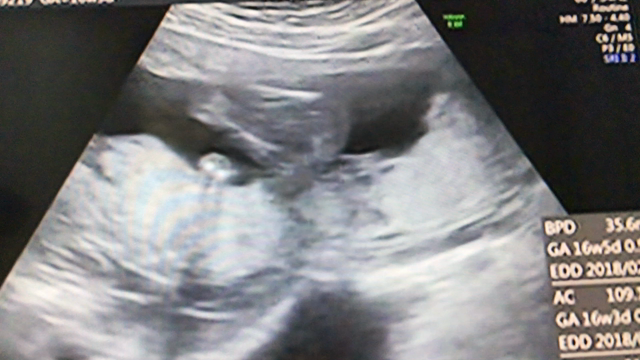

妊婦健診*2 エコー動画と性別

2017年8月24日